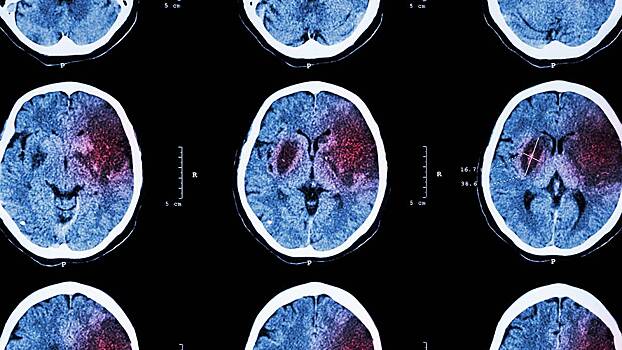

Кардиолог предупредил о рисках инсульта из-за сидячего образа жизни

Каждый час в положении сидя в пожилом возрасте повышает риск инсульта на 14 процентов. Об этом заявил кардиолог Олег Варфоломеев.

«Малоподвижный образ жизни может поставить под угрозу ваше здоровье. Каждый час, проведенный в сидячем положении в возрасте 60–70 лет, увеличивает риск инсульта на 14 процентов. Все — от просмотра телевизора до расслабления — может повысить вероятность развития тяжелого состояния. Если вы не двигаетесь в течение 13 и более часов в день, то ваш риск инсульта на 44 процента выше, как показывают исследования»,